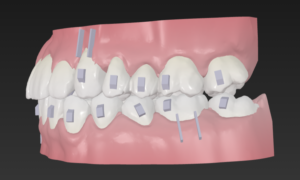

データから歯科医がゴールを設定

あとはAIが0.2ミリずつ歯並びを変えて

マウスピースを作成

この歯並びの治し方は

歯と歯の間を少し削りスキマを作り

歯をキレイに整列

この時

上の歯は少し多めに歯と歯の間を削り

でっ歯を改善

患者様は気づいていませんが

実は上下の正中は大きくズレていて

これを片側にⅢ級ゴムを装置して矯正